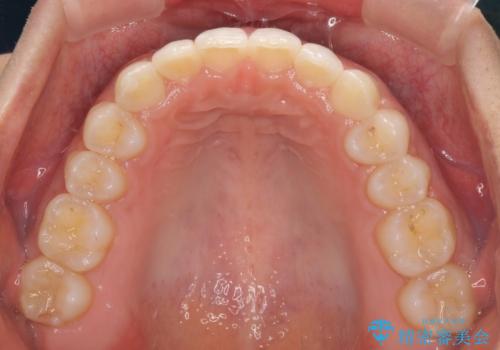

- 深い咬み合わせ(ディープバイト)と前歯のデコボコを気にして来院された患者様です。

インビザラインによる上下歯列の側方拡大と後方移動、IPR(歯と歯の間を削る)にるスペースの獲得により、デコボコとディープバイトを改善することとしました。

1日22時間の装着時間をしっかり守ってくださったので、予定通り1年で治療を終えることができました。

ディープバイトによる食いしばり癖も解消され、患者様には大変満足していただきました。